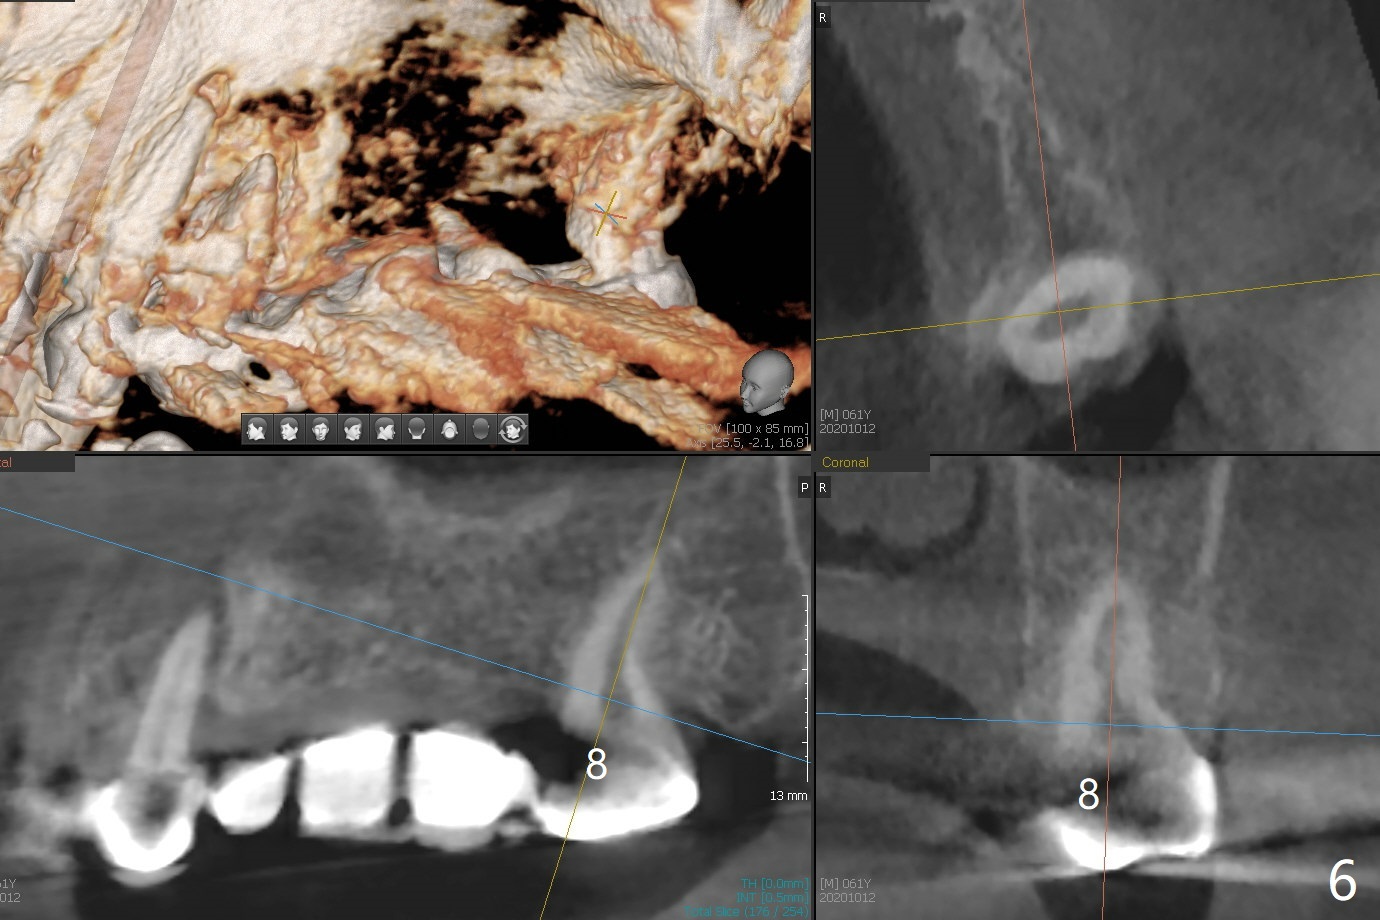

61男牙齿不好,左上4-8牙桥松动(图一,五,六),右下2,左下3根尖瘘道(图二),左上4,8也需要根管治疗,以上牙齿以及右下3插入球状牙桩(图一:*),然后在右上,左下,右下7植牙,放置球状基台(图一:箭头),固定上下活动义齿(覆盖义齿)。下前牙颊侧骨板几乎没有(图七)。左下7骨头(图八)宽于左下5(图三)。